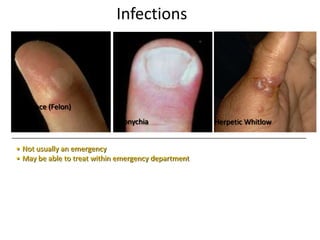

- Conditions that require emergency referral are discussed, such as bleeding, amputation, replantation, compartment syndrome, infections, and high pressure injection injuries. Proper management of these conditions focuses on rapid assessment and treatment to prevent further tissue damage.